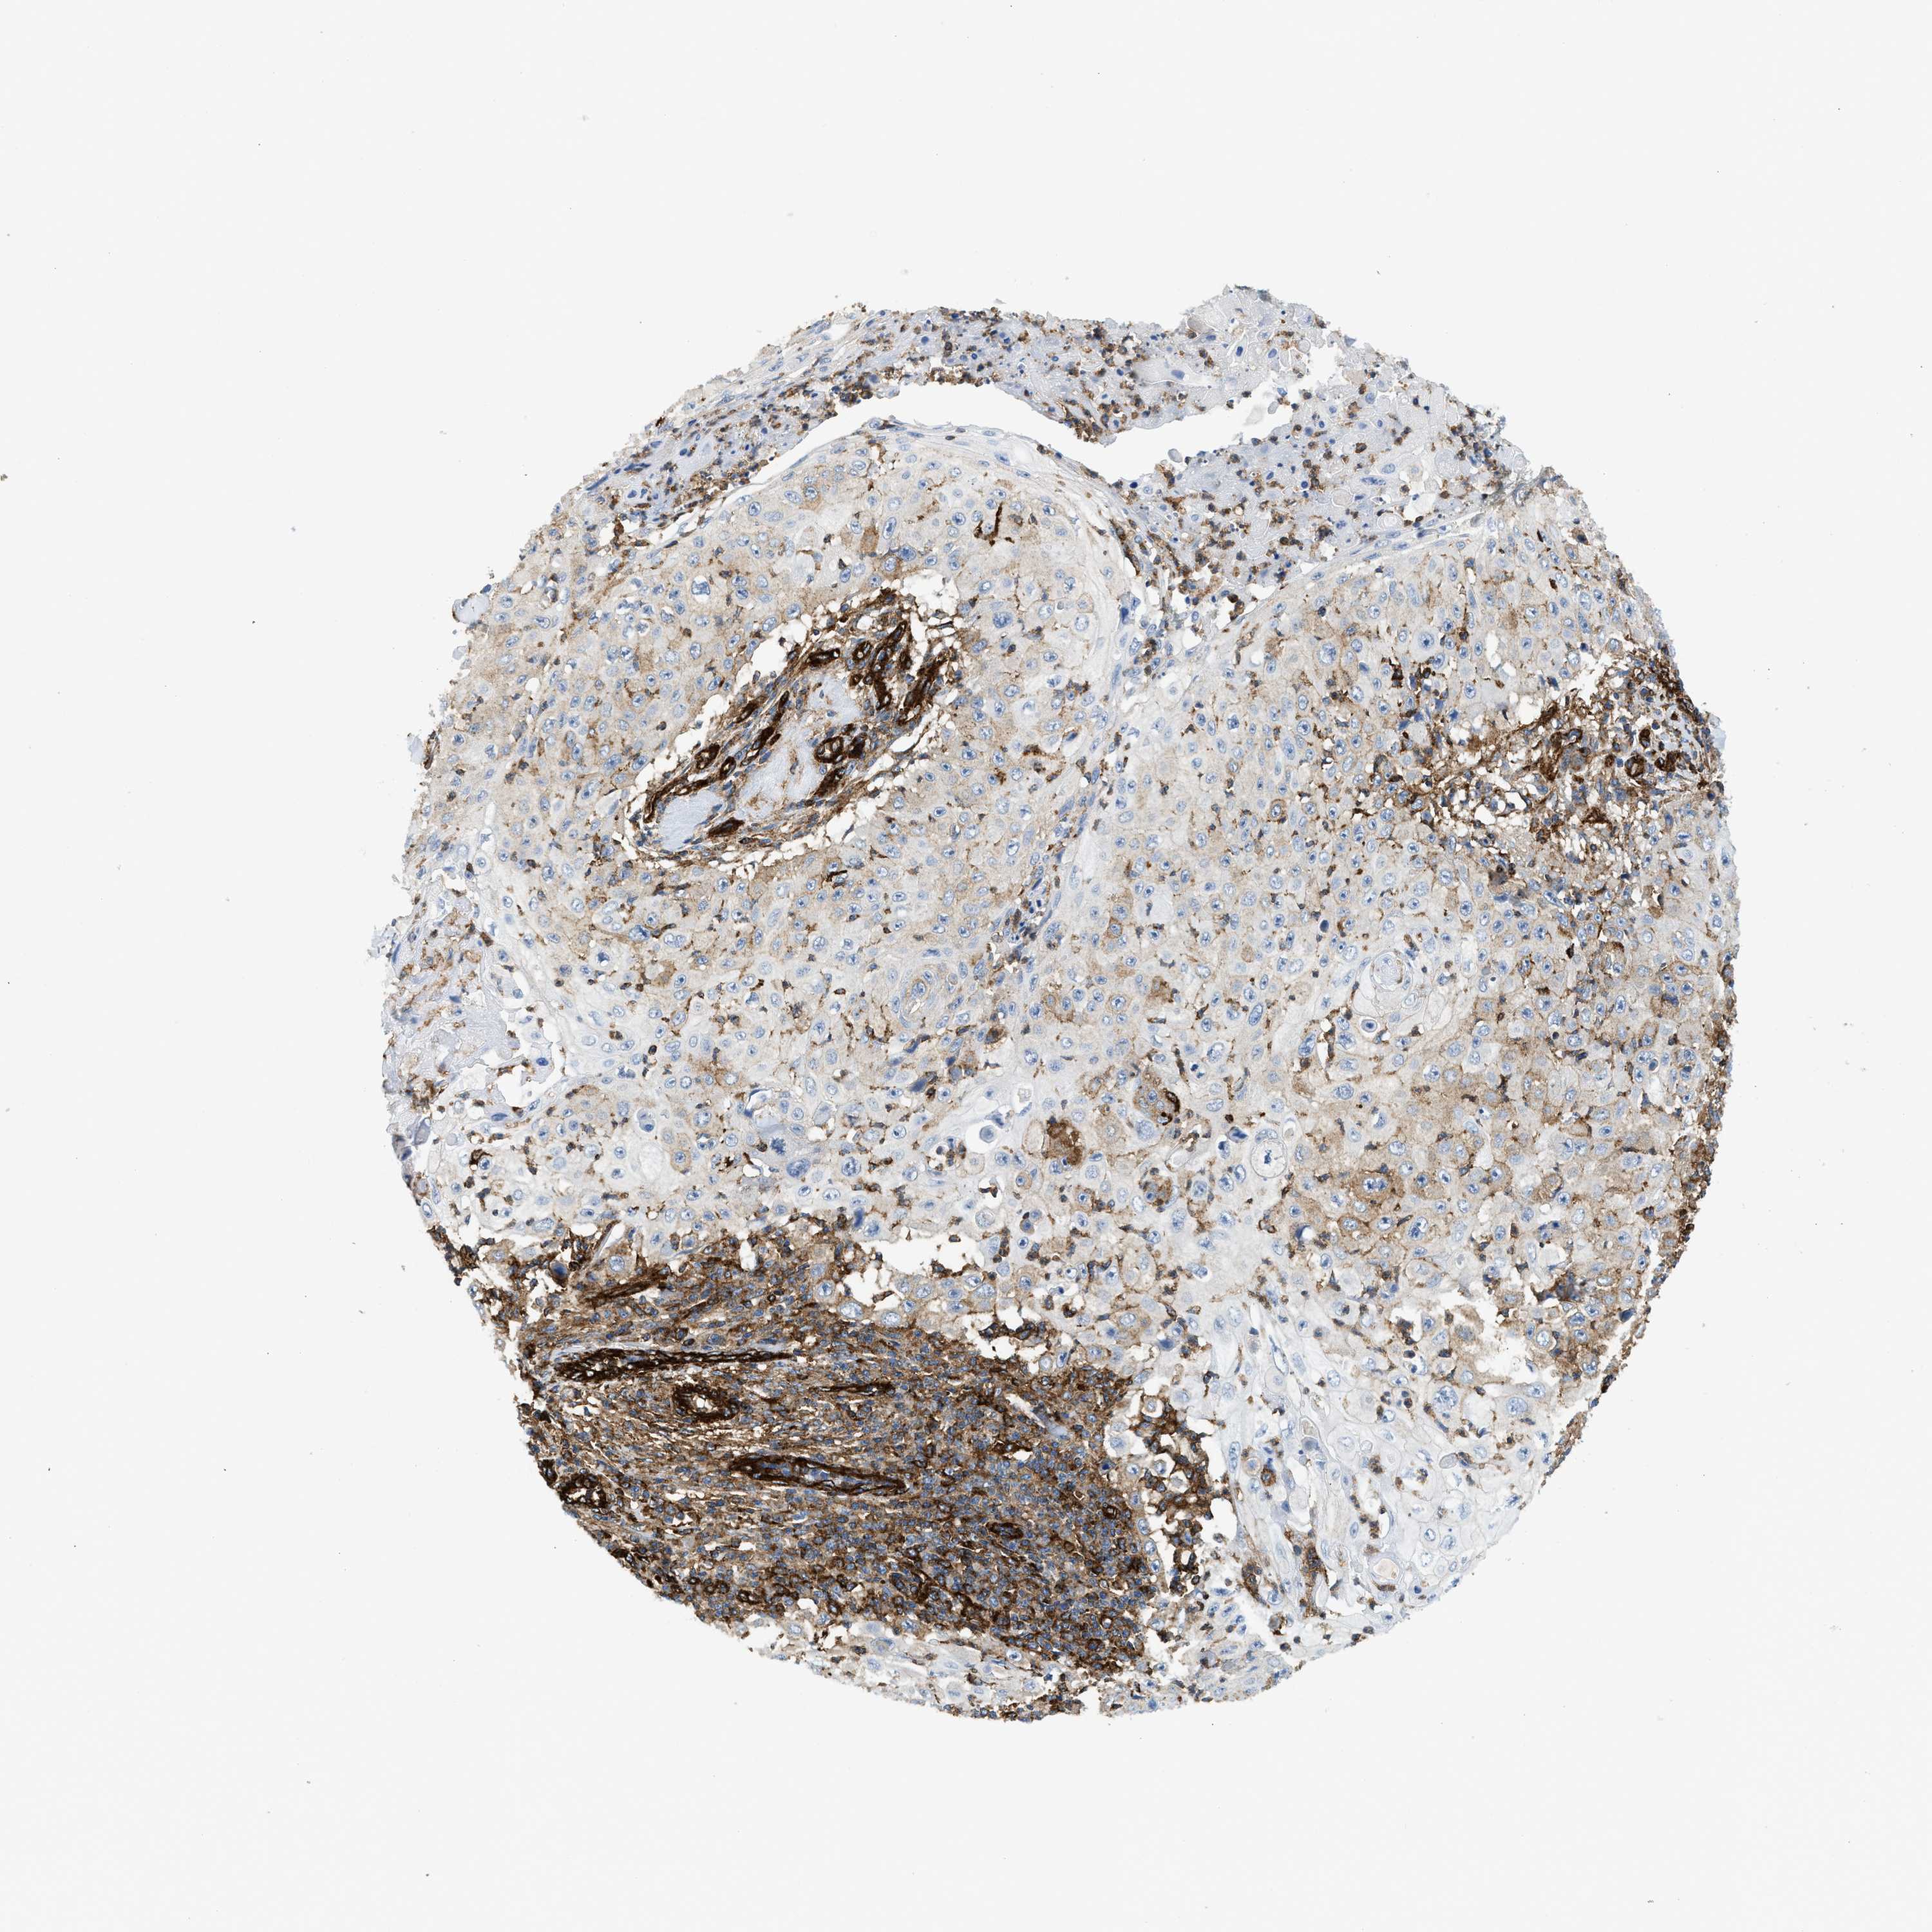

SKIN CANCER - Protein expressioni

A mouse-over function shows sample information and annotation data. Click on an image to view it in a full screen mode. Samples can be filtered based on level of antibody staining by selecting one or several of the following categories: high, medium, low and not detected. The assay and annotation is described here.

Antibody stainingi

Antibody staining in the annotated cell types in the current human tissue is reported as not detected, low, medium, or high, based on conventional immunohistochemistry profiling in selected tissues. This score is based on the combination of the staining intensity and fraction of stained cells.

Each image is clickable and will lead to virtual microscopy that enables deeper exploration of all samples and also displays staining intensity scores, fraction scores and subcellular localization as well as patient and tissue information for each sample.

Antibody HPA013606

Staining

High

Medium

Low

Not detected

Intensity

Strong

Moderate

Weak

Negative

Quantity

>75%

75%-25%

<25%

None

Location

Nuclear

Cytoplasmic/membranous

Cytoplasmic/membranous,nuclear

Squamous cell carcinoma, NOS